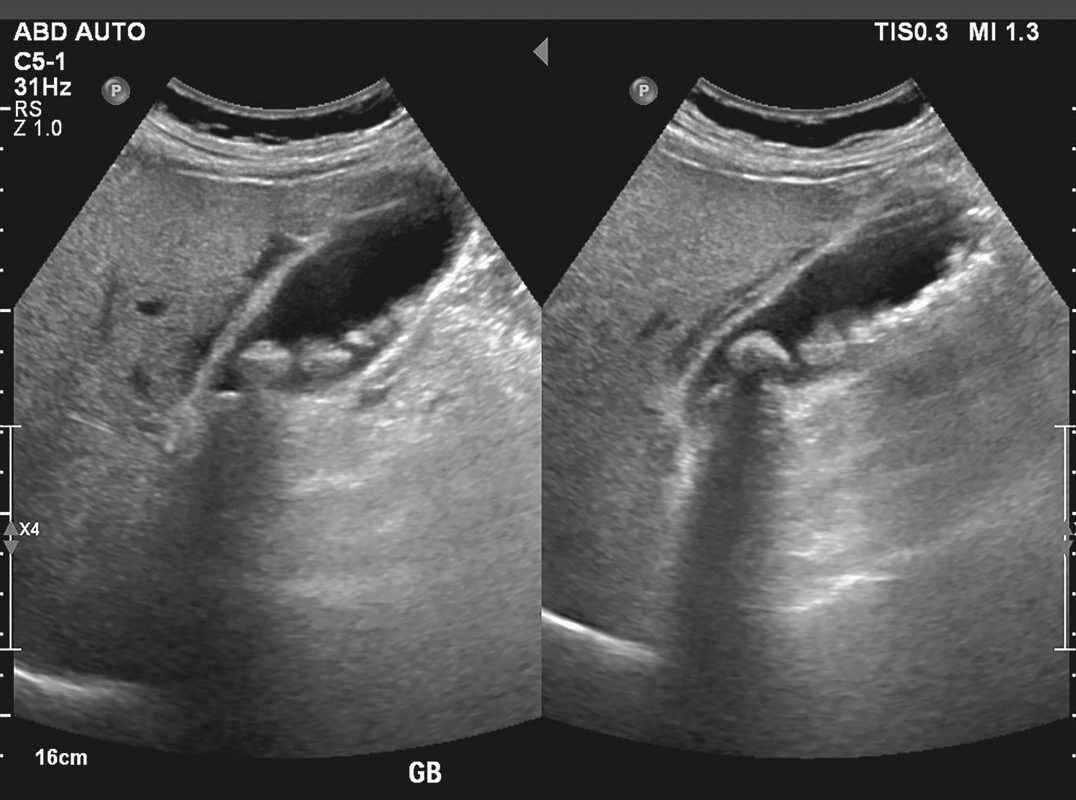

There is a little organ called the gallbladderin your upper right belly, directly beneath your liver. Bile, a greenish-yellow liquid that aids in digestion, is kept in this pouch. Sometimes, gallstones obstruct the bile duct. Most gallstones are caused by the hardening of bile-derived chemicals like cholesterol. Gallstones are often asymptomatic and quite prevalent. However, only 10% of those with gallstones will have symptoms within 5 years.

Gallstones themselves don’t cause pain. Instead, discomfort happens when gallstones obstruct bile flow from the gallbladder.”Silent gallstones” affect roughly 80% of people with gallstones. So the vast majority are symptom- and pain-free.